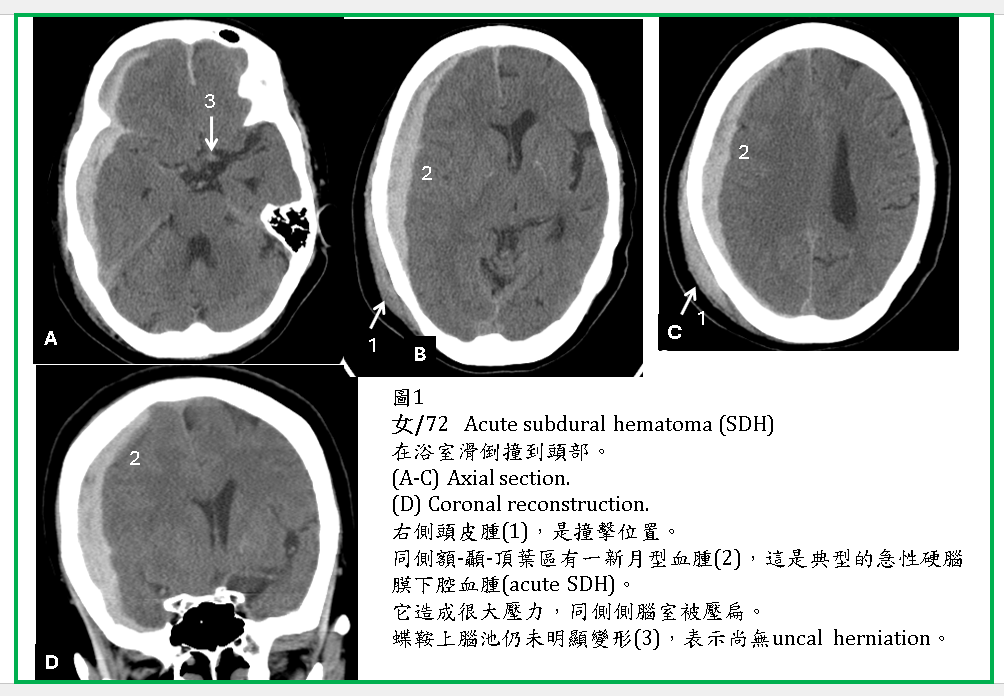

CT形狀:

典型的ASDH呈現鐮刀形或新月形的高濃度區域(圖1,2) ,因它會往前後滲透,所以厚度不會太厚,可是腫塊效應也是很強,嚴重時也會造成uncal及transtentorial herniations (圖2,3) 。

ASDH有時往後會延伸到小腦天幕下的硬腦膜下腔(圖1-3)。在CT橫切面,小腦天幕下SDH呈現片狀,極易被誤為是腦內血塊(ICH) (圖3,4)。SDH有時會在大腦半球間裂(interhemispheric fissure) (圖5),或由大腦額頂葉外的SDH滲透進入interhemispheric fissure 。